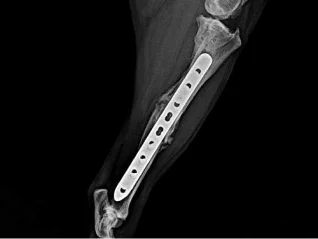

View PathwayTrauma & Fracture Repair